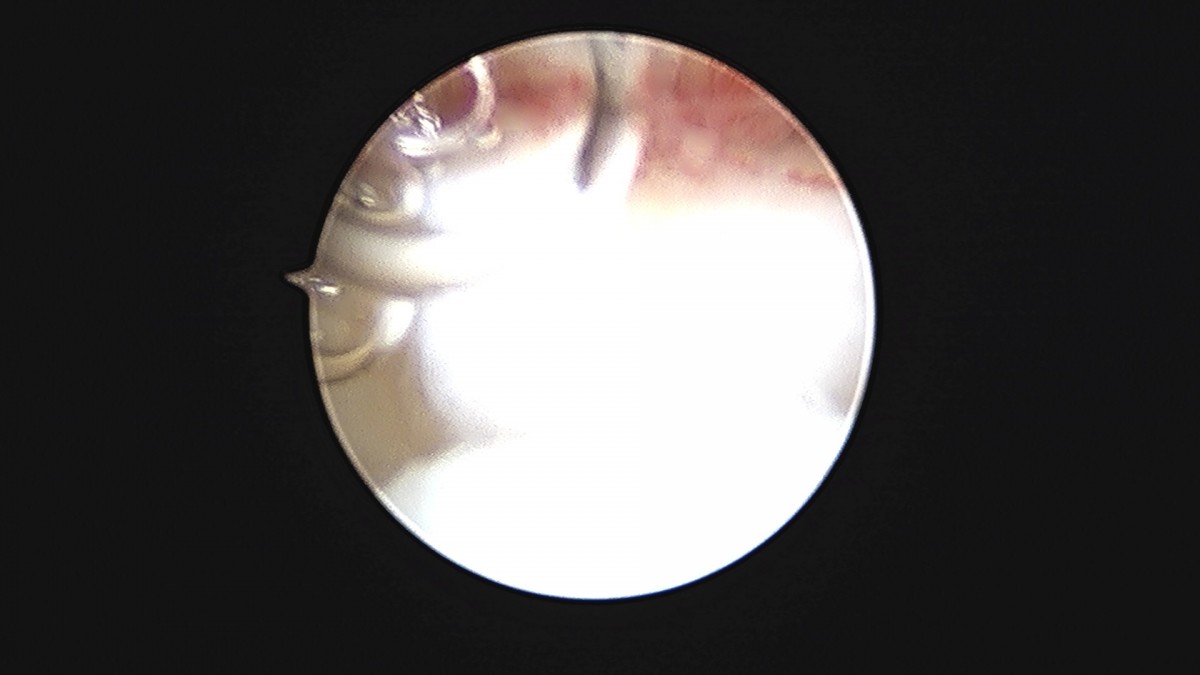

이재상원장님 발목 연골병변 제거술 및 골수 자극술 장경O 환자

dae765e4d9ac96aee867c9d6292d8784_1758006811_9585.jpg